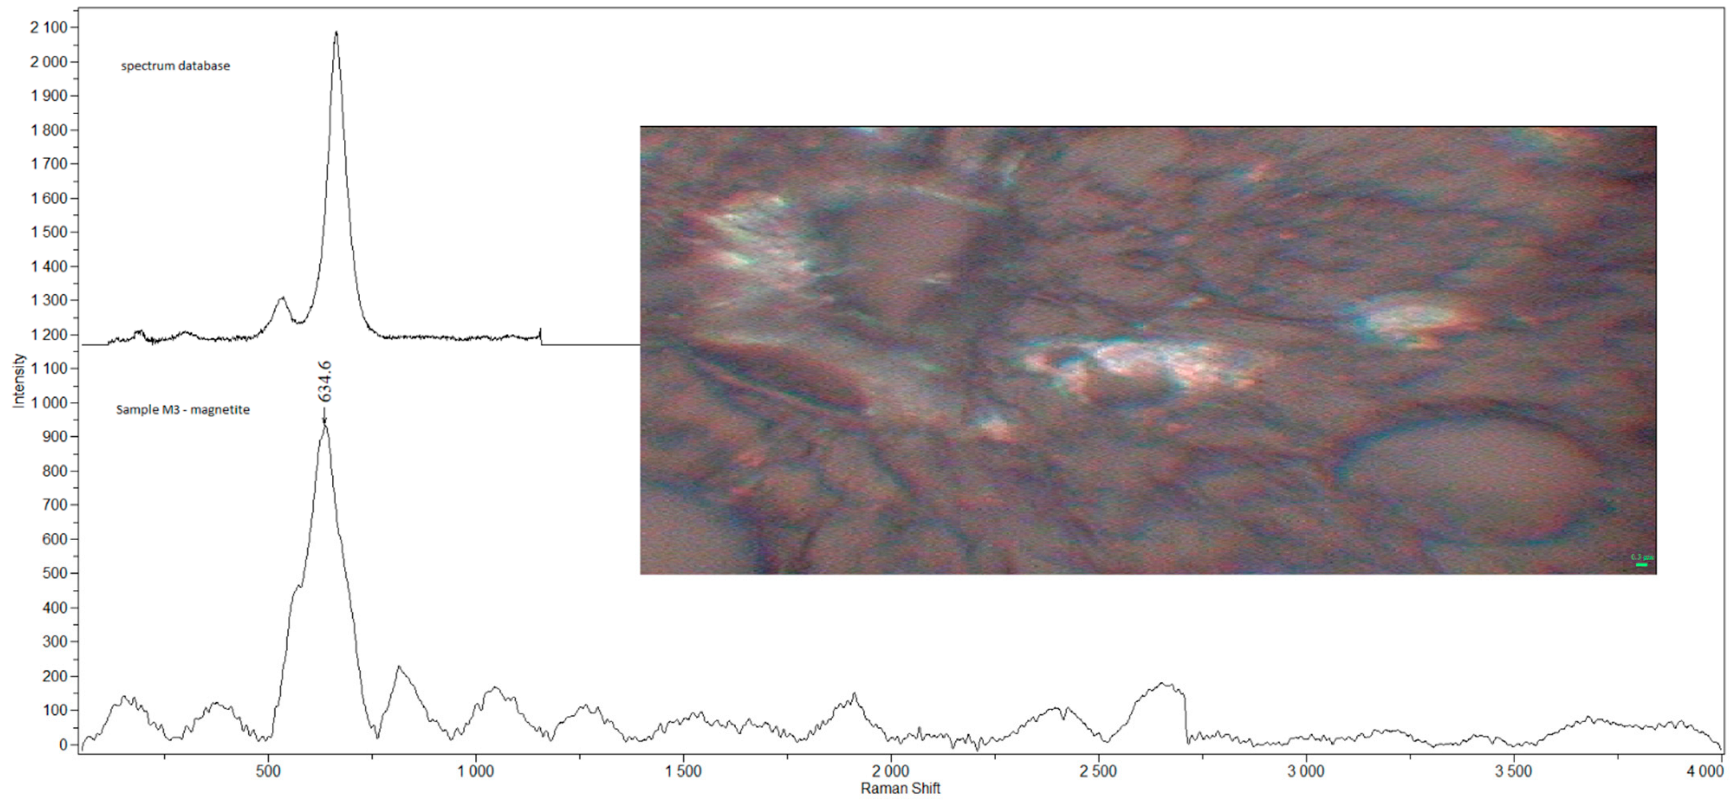

2.2. Raman Microspectroscopy

3.1. Detected Compounds

- Čabanová, K.; Motyka, O.; Bielniková, H.; Čábalová, L.; Handlos, P.; Zabiegaj, D.; Zeleník, K.; Dvořáčková, J.; Komínek, P.; Heviánková, S.; et al. Identification of the phase composition of solid microparticles in the nasal mucosa of patients with chronic hypertrophic rhinitis using Raman microspectroscopy. Sci. Rep. 2021, 11, 18989. [Google Scholar] [CrossRef] [PubMed]

- Čabanová, K.; Peikertová, P.; Bielniková, H.; Barošová, H.; Motyka, O.; Čábalová, L.; Dvořáčková, J.; Komínek, P.; Kukutschová, J. Raman microspectroscopy as a useful tool for nanopathology. J. Raman Spectrosc. 2017, 48, 357–362. [Google Scholar] [CrossRef]

| M3 | m | 38 | N | welder (M) | AC, CaSO4, Fe3O4, GR, TiO2-A | 1 |